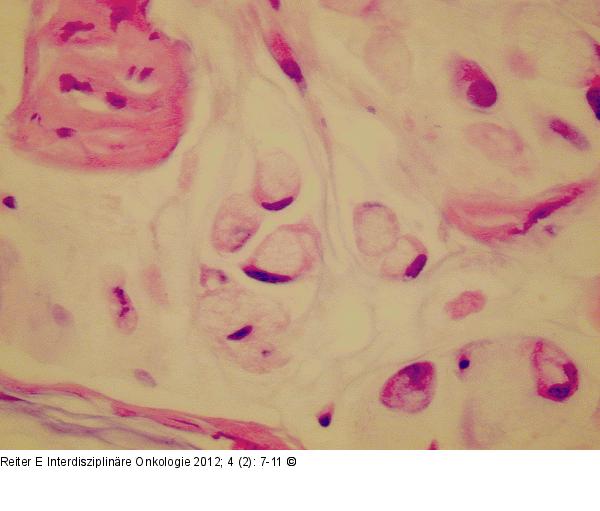

Abbildung 5: Pseudomyxoma peritonei Hochgradiges Pseudomyxoma peritonei: Schleimsee mit eingelagerten Siegelringzellen. |

Abbildung 5: Pseudomyxoma peritonei

Hochgradiges Pseudomyxoma peritonei: Schleimsee mit eingelagerten Siegelringzellen. |